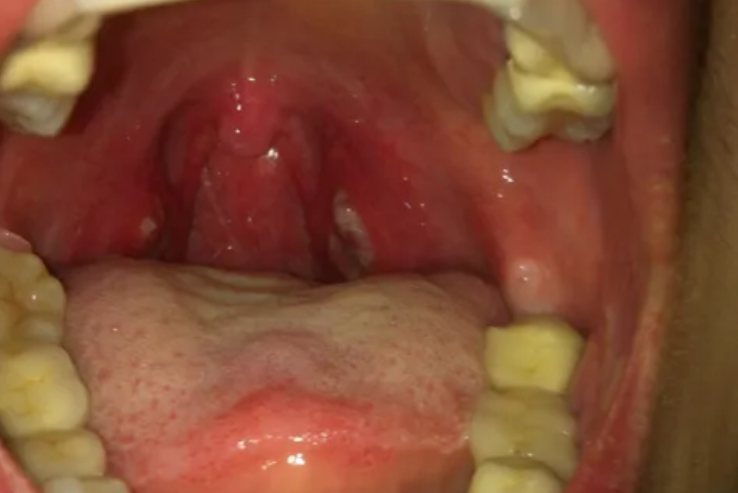

扁桃体化脓即指化脓性扁桃体炎,为临床常见的上呼吸道感染性疾病之一,主要由非溶血性链球菌、葡萄球菌等细菌感染引起,部分也与腺病毒、鼻病毒等感染有关,可表现有局部咽部剧烈疼痛、高热、放射性耳后疼痛等。

以咽部出现剧烈疼痛为主,咽痛可持续超过两天,常伴有吞咽困难。如果发病为婴幼儿,多出现拒食、流口水表现,严重者可出现呼吸困难。

包括放射性的耳后疼痛、说话时语言含糊、下颌淋巴结肿大伴压痛、夜间憋醒或打鼾等。